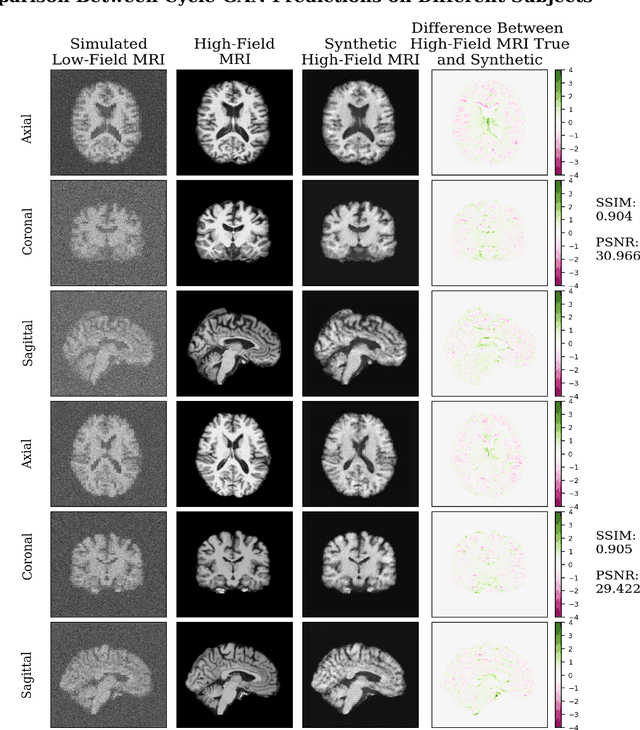

In this work, a denoising Cycle-GAN (Cycle Consistent Generative Adversarial Network) is implemented to yield high-field, high resolution, high signal-to-noise ratio (SNR) Magnetic Resonance Imaging (MRI) images from simulated low-field, low resolution, low SNR MRI images. Resampling and additive Rician noise were used to simulate low-field MRI. Images were utilized to train a Denoising Autoencoder (DAE) and a Cycle-GAN, with paired and unpaired cases. Both networks were evaluated using SSIM and PSNR image quality metrics. This work demonstrates the use of a generative deep learning model that can outperform classical DAEs to improve low-field MRI images and does not require image pairs.